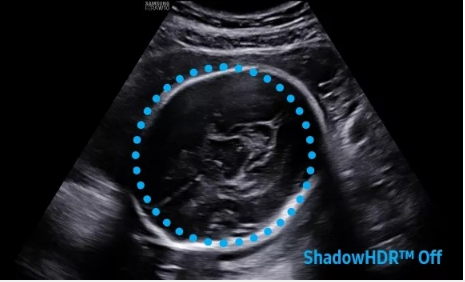

2D成像方面,Hera i10集成了包括ShadowHDR?、HQ-Vision?、ClearVision等多項(xiàng)具有三星“血統(tǒng)”的技術(shù),加強(qiáng)了圖像的陰影抑制、減少偽影、緩和模糊區(qū)。